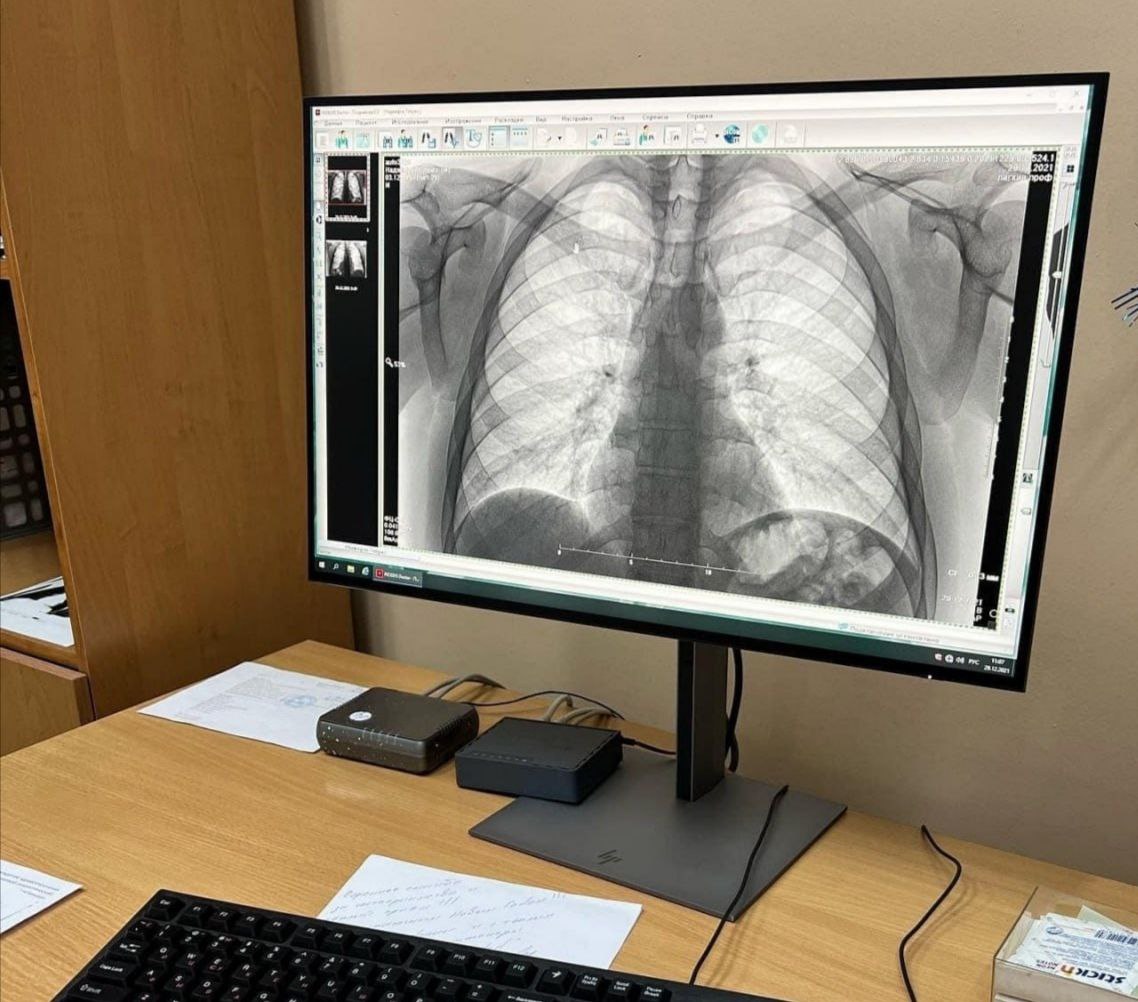

В преддверии Всемирного дня борьбы с туберкулезом в Забайкальском фтизиопульмонологическом центре 22 марта пройдет день открытых дверей. С 10.00 до 12.00 забайкальцы смогут сделать иммунодиагностический тест, а с 10.00 до 16.00 - пройти бесплатный осмотр фтизиатра и флюорографию. С 14.00 до 15.00 на площади имени Ленина состоится ежегодная акция «Белая ромашка» - врачи расскажут про заболевание и методы лечения.

«Врачи центра оценят результаты обследования, дадут рекомендации по ведению здорового образа жизни. При выявлении подозрения на заболевание легких будут проведены дополнительные исследования и назначено лечение. Раннее выявление заболеваний и своевременное начало лечения - это верный шаг к сохранению здоровья», - отметила исполняющая обязанности главного врача учреждения Татьяна Кнестикова.